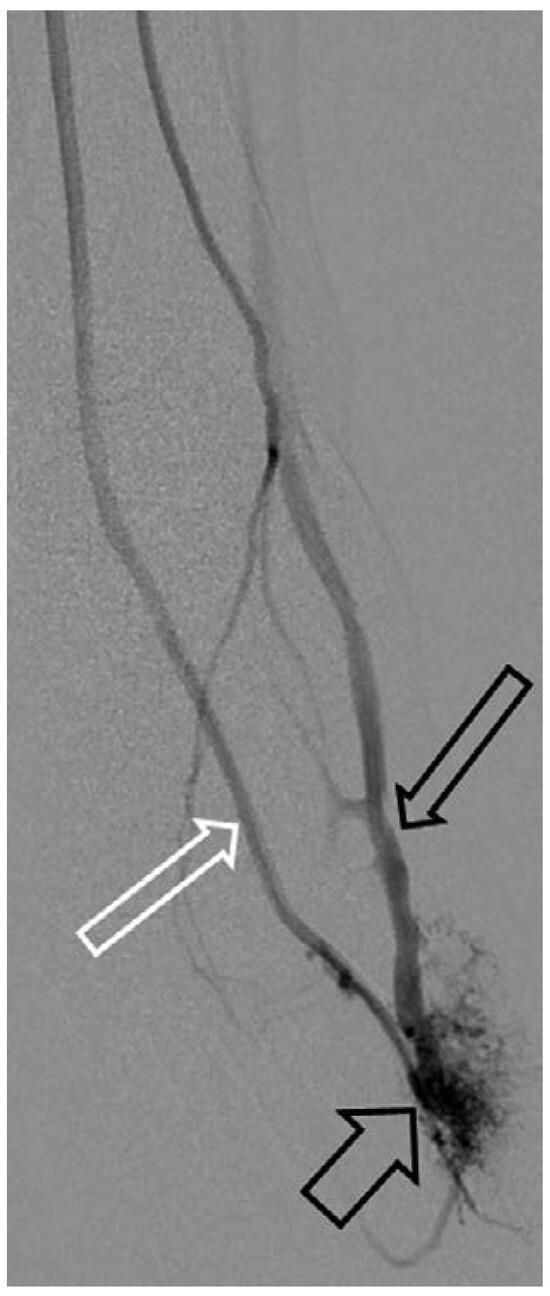

Case report A 22-year-old male experienced a presyncopal spell while studying for a university examination [...]